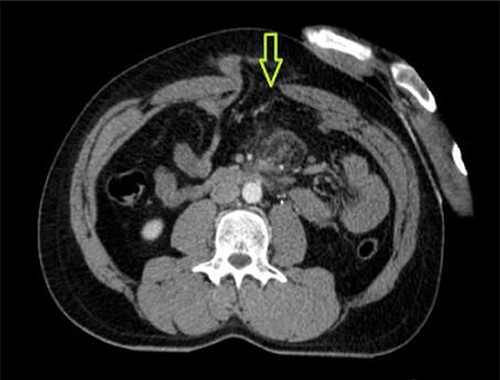

A 41-year-old man presented to the emergency room soon after falling from his motorcycle and hitting his handlebars in the epigastric region. The patient’s vital signs and initial laboratory studies were normal. Physical examination showed a soft tissue bulge in the epigastric region with superficial ecchymosis and tenderness to palpation. The swelling was obvious on standing and less evident when lying supine (Fig. 1). Focused Assessment with Sonography for Trauma (FAST) performed in the emergency room did not show free fluid in the abdominal cavity. Computed tomography (CT) scan showed intestinal loops protruding through a defect in the abdominal wall into the subcutaneous space (Figs 2 and 3). Therefore, a surgical approach for handlebar hernia treatment was decided on the first day of hospitalization. A defect throughout the entire abdominal wall, including the fascia, muscular layers and peritoneum, with bowel protruding into the subcutaneous space, was observed during surgery (Fig. 4). There was no blood or fecal contamination in the area immediately surrounding the lesion, and exploration of the bowel loops did not reveal signs of intra-abdominal injury. Based on this, hernia repair was performed with prosthetic material (Fig. 5). As there was no evidence of intra-abdominal injury, local wound exploration provided the best anatomic layered repair with subsequent minimal residual defect and improved long-term cosmesis. The defect was repaired in layers, and the patient postoperative course was uneventful.

CT abdomen showing abdominal wall hernia containing a loop of small intestine (green arrow).